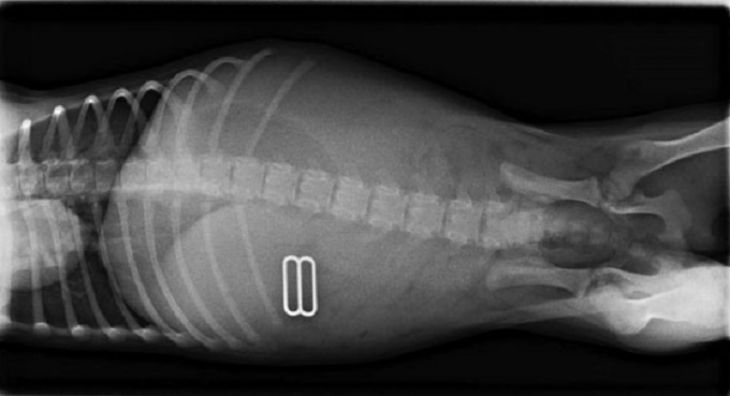

Deväť golfových loptičiek a guľka

Bertieho majitelia prichytili svojho miláčika pri konzumovaní golfových loptičiek. Ihneď s ním utekali na veterinárnu pohotovosť. S prekvapením zistili, že sa mu podarilo prehltnúť až 9 týchto loptičiek a pochutnal si tiež na jednom broku z brokovnice.

(Zdroj: PopSugar)